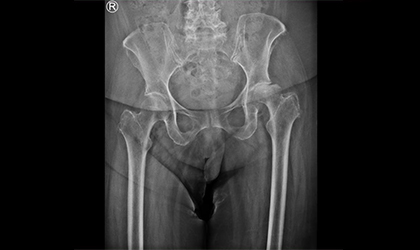

This 82-year-old lady, mother of a doctor, developed sudden and rapidly worsening hip pain over the course of a month. Initial concerns pointed to a possible infection due to the rapid collapse of the joint. Further evaluation confirmed a rare condition — rapidly progressive osteoarthritis, which is effectively treated with a single-stage hip replacement.We used a dual mobility here to reduce the risk of dislocation. She was in hospital for 3 days and is delighted with the results as she is pain free and back to normal mobility

The rapid deterioration of the hip joint initially mimicked an infection. However, it was diagnosed as rapidly progressive osteoarthritis — a rare but treatable condition.

To minimize the risk of dislocation, a dual mobility implant was used during the single-stage hip replacement procedure.